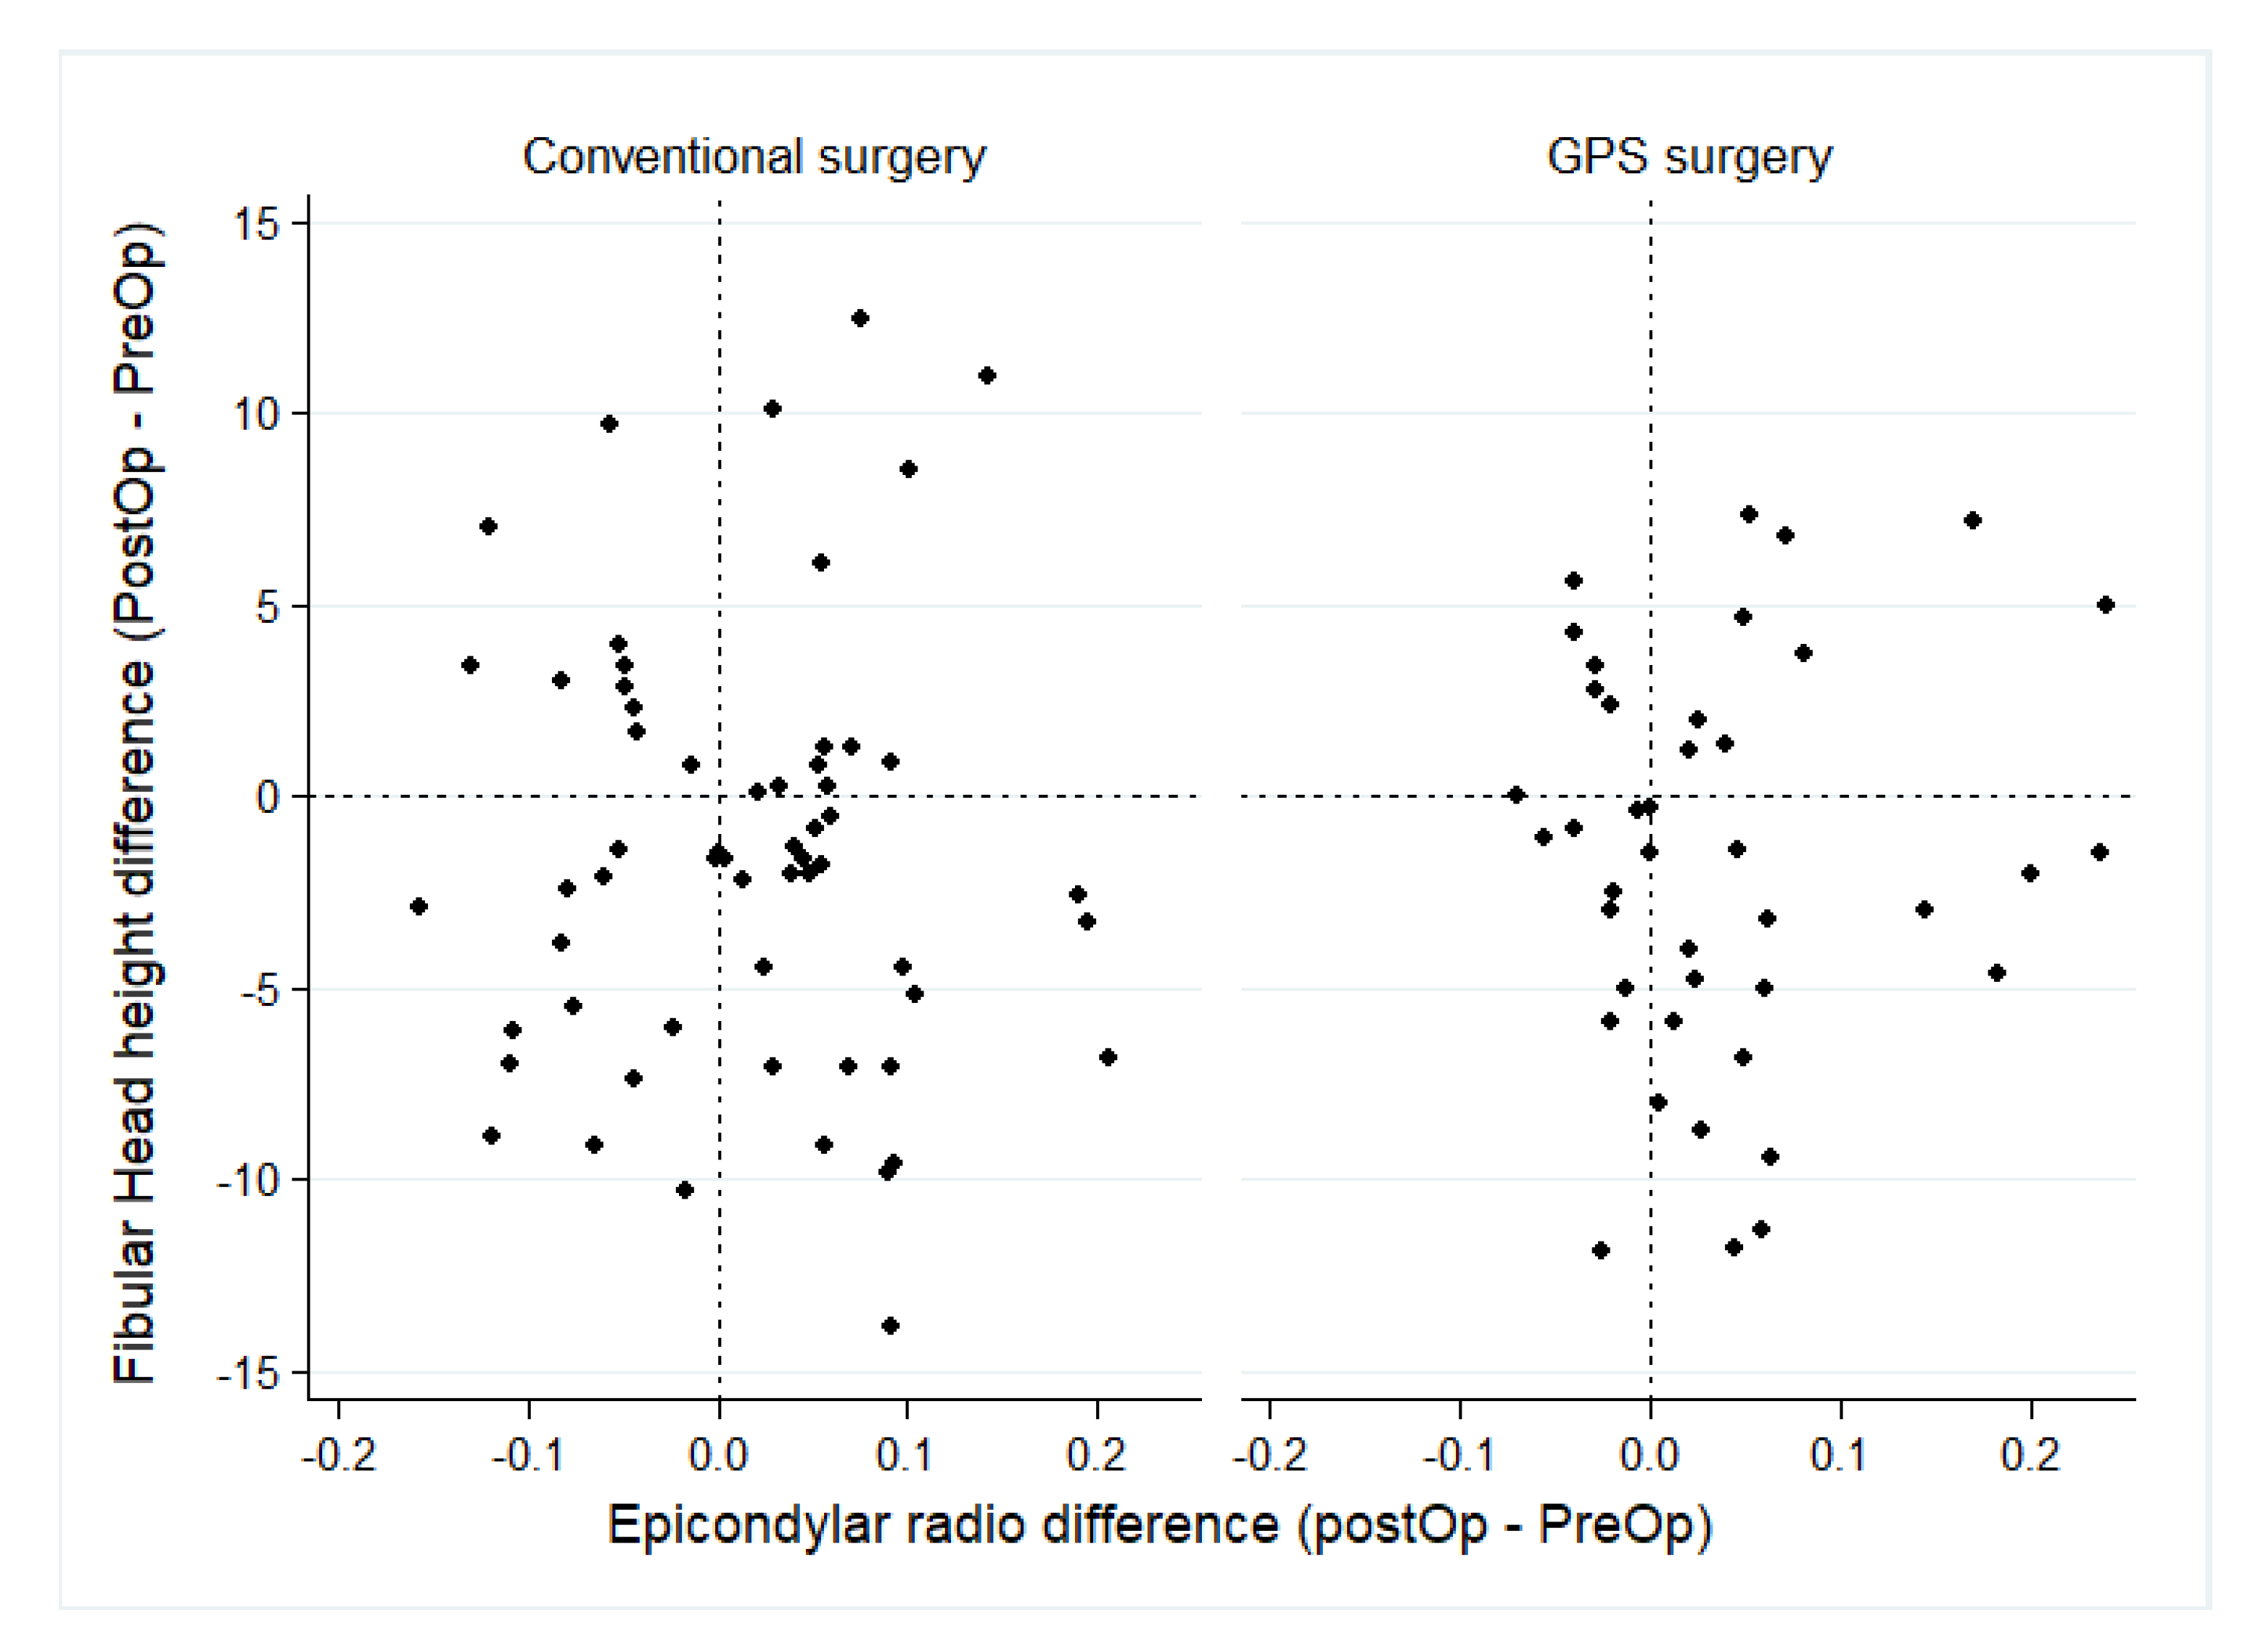

| Articular Joint Line | Measure Time | Conventional Surgery n = 59 (Mean ± SD) | GPS Surgery n = 41 (Mean ± SD) | Mean Comparison, by Surgery | Variance Comparison, by Surgery |

| ER | Pre-Operative | 0.62 ± 0.1 | 0.63 ± 0.1 | p = 0.378 z | p = 0.450 w |

| Post-Operative | 0.63 ± 0.1 | 0.66 ± 0.1 | p = 0.004 z | p = 0.004 w | |

| Pre-Post mean comparison | p = 0.179 pt | p = 0.004 pt | |||

| Pre-Post variance comparison | p = 0.289 f | p = 0.317 w | |||

| FH | Pre-Operative | 17.6 ± 5.1 | 17.3 ± 5.3 | p = 0.795 t | p = 0.791 f |

| Post-Operative | 16.1 ± 4.3 | 15.7 ± 3.8 | p = 0.634 t | p = 0.451 f | |

| Pre-Post mean comparison | p = 0.045 pt | p = 0.028 pt | |||

| Pre-Post variance comparison | p = 0.186 f | p = 0.044 f |